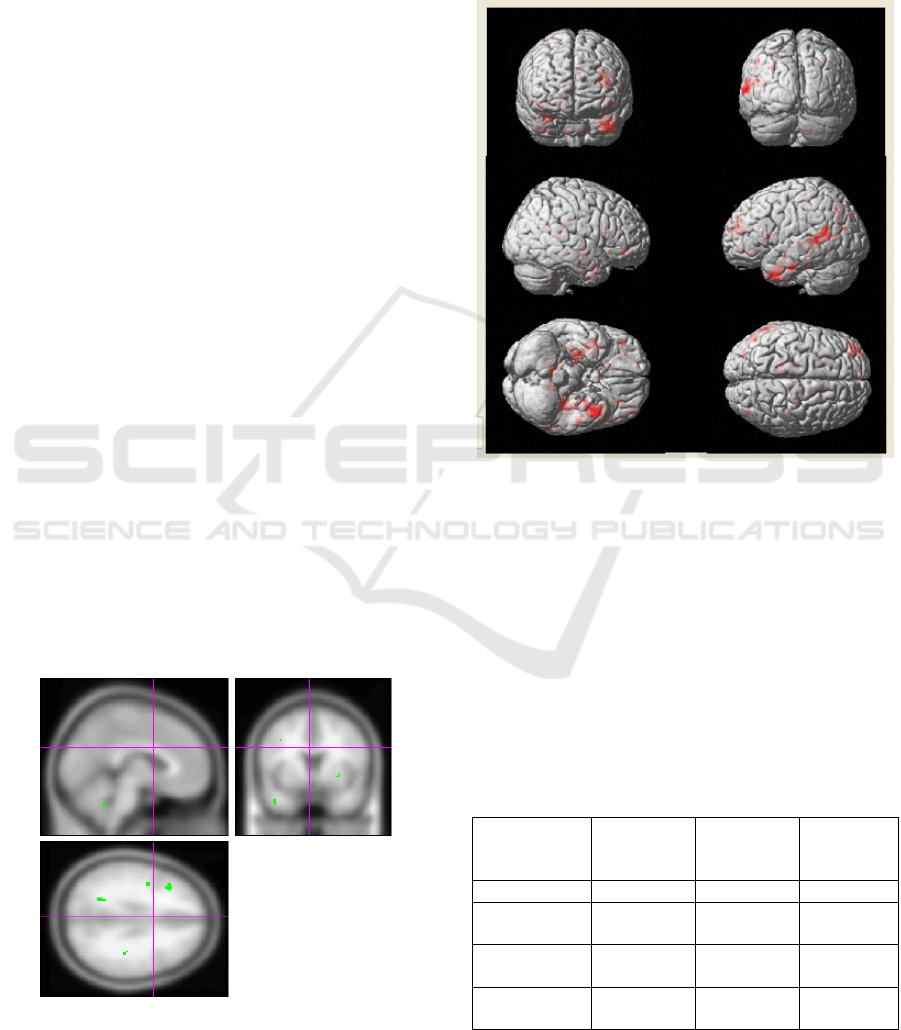

Group comparison analysis allows to identify

certain brain regions with different activation

patterns. Patients with Alzheimer's disease showed

less activation in hippocampal formation (HF) and

parahippocampal gyri comparing to healthy controls

group (p<0.05). The study also showed reduced

activation in posterior cingulate gyrus (p<0.001).

Figure 1: Reduced activation in posterior cingulated gyrus

and in hippocampal formation region in AD patients

(p<0.001).

Figure 2: Differences in activation between AD group and

healthy controls (three-dimensional volume-rendered

display).

Voxel-based morphometry showed significant

general atrophy of grey matter in AD patients,

especially of both temporal lobes (fusiform and

parahippocampal gyri), frontal lobes (and superior

frontal gyri), parietal lobes and cingulate gyrus.

Figure 3: Brain atrophy in Alzheimer's disease patients

comparing to the control group (p<0.001).